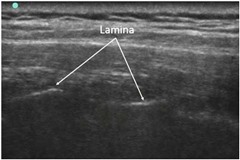

実際のエコー画像をお見せします。

下図は、背部正中線から約1.5cm外側で、脊椎に平行にプローブを当てたものです。

傍脊椎ブロック,retrolaminar block,paravertebral block,椎弓板

白く光ってみえるのが椎弓版のところです。